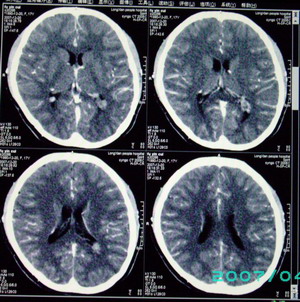

以下是引用九目段在2007-12-24 14:55:00的发言:[br]1,年轻女性[br]2,ct表现:左侧脑室三角区可见一不规则小明显强化的结节,中央见小低密度,侧脑室无扩张。[br]分析:[br]常见的有三种肿瘤好发三角区:[br]1,脉络丛乳头状瘤,好发于年轻者,明显强化,实性,分泌脑脊液,常伴有侧脑室扩大,肿瘤较小可以脑室扩大不明显,不能排除,但小结节尚不易形成坏死腔。[br]2,室管膜瘤,好发于儿童及青少年,明显强化,易坏死,大时伴脑室扩张。[br]3,脑膜瘤,明显强化,圆形,界请,无脑积水,一般不坏死。[br]诊断:[br]左侧脑室三角区结节,考虑室管膜瘤可能性大,不排除脉络丛乳头状瘤和脑膜瘤(因病史较长)。[br][br][本贴已被 九目段 于 2007-12-24 15:13:35 修改过]